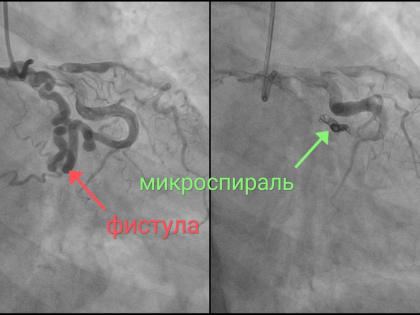

Пожилой новгородке в НОКБ сделали уникальную операцию на сердце

Медики регионального сосудистого центра осуществили уникальную хирургическую операцию на сердце.